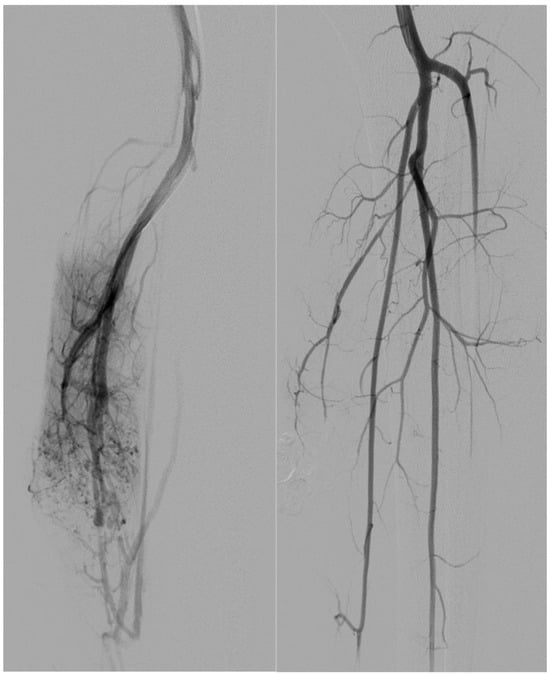

Five patients with Type IV arteriovenous malformations underwent both arterial and venous embolization; all lesions were located in the lower extremity.

On the arterial side, embolic materials were distributed as follows: coils alone in one patient (20%) (Figure 2), a combination of coils and ethylene vinyl alcohol copolymer (EVOH) in one (20%) (Figure 3), EVOH alone in one (20%), and polyvinyl alcohol particles (PVA) alone in one (20%).

Figure 2. A 31-year-old patient presents with a Type IV AVM from the collateral branch of the gluteal artery. The left image shows an angiographic examination performed pre-procedure after super-selective catheterization of the vessel using a Progreat microcatheter. The image on the right shows post-embolization angiography performed using 4 mm coils.

Figure 3. A 33-year-old patient presents with a Type I AVM from the collateral branch of the uterine artery. The left image shows an angiographic examination performed pre-procedure after super-selective catheterization of the vessel using an RUC catheter and a Progreat microcatheter. The image on the right shows post-embolization angiography performed using three 6 mm Nester coils and injecting EVOH.